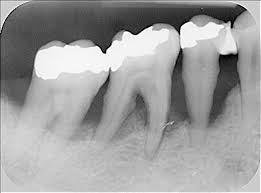

10 Irrtumer Uber Weisheitszahne Gesundheit Bild De

10 Irrtumer Uber Weisheitszahne Gesundheit Bild De from bilder.bild.de

Doch nicht immer müssen weisheitszähne gleich entfernt werden. Wenn es zeit ist, dass der bleibende zahn durchbricht und er auf einem röntgenbild zu sehen ist, wird der zahnarzt den angegriffenen milchzahn daher entfernen. Was ist das zahn ziehen? Nicht einfach zahn ziehen lassen. Vereinbaren sie einen kurzfristigen kontrolltermin in unserer ihre fragen zur zahnextraxtion. Das ziehen des zahnes ist. Wann ist es ratsam einen zahn zu entfernen? Die meisten zähne, die in deutschland gezogen werden, sind der volkskrankheit karies (zahnfäule) oder der parodontitis (entzündung und zerstörung des zahnhalteapparats) zum opfer gefallen.